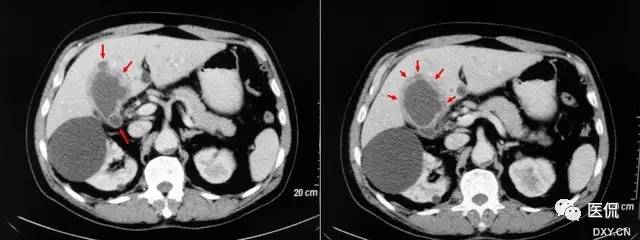

19 珍珠项链征又名珍珠项圈征

【影像表现】在CT或MRCP及T2W I上增厚的胆囊壁中多发、微小圆点状的高信号囊腔,大小2~7mm,一般为4mm,形似珍珠项圈。

【征象解释】胆囊肌层及上皮增生、肥大,粘膜外翻进入肌层形成罗-阿氏窦。因为罗-阿氏窦内充满胆汁,在MRCP或T2WI增厚的胆囊壁内可呈显著高信号点。

【讨论】胆囊腺肌瘤病是胆囊上皮及肌层增生,粘膜向增厚的肌层内突出或穿过肌层形成罗-阿氏窦,是胆囊的一种常见疾病。发病率为2.8%~5%或更高,常表现为胆囊壁的局限性或弥漫性增厚,因此必须与胆囊癌鉴别。

胆囊腺肌瘤病有3种分型:弥漫型、节段型、局限型。因为有这种形态变异,它可表现为弥漫性胆囊壁增厚或局限性、局灶性损害,可能被误以为胆囊癌口因此,胆囊腺肌瘤病与胆囊癌的影像学区别是非常重要的口病理学上,胆囊腺肌瘤病的特征表现是增厚的胆囊肌层中看到罗-阿氏窦,罗-阿氏窦的发现是诊断胆囊腺肌瘤病的关键点。

在静脉胆道造影中充满造影剂的罗-阿氏窦被认为是胆囊腺肌瘤病的特异性病征,也称为珍珠项链征。然而,罗-阿氏窦的显示率相对较低(大约5%),因为胆囊不可能一直充满造影剂。虽然,静脉胆道造影检查前服脂肪餐可能改善罗-阿氏窦的显示,但还是不够;而且,静脉胆道造影用的造影剂频繁发生变态反应,有时可能导致过敏性休克口目前,对于胆囊疾病的非创性且方便的检查方法首选US。虽然US对胆囊腺肌瘤病的诊断有一定的敏感性,但因为它依赖操作者的经验,所以有一定的不确定性,其观察视野小、肠道气体、肥胖及与结石共存使US在胆囊壁的评估仁有一定困难。因此,Us在胆囊腺肌瘤病的诊断准确率只有60%。

CT及MRI可发现胆囊壁的局限性或弥漫性增厚,以及病变处勒膜层的早期强化和浆膜层的延迟强化,但很难与胆囊炎和胆囊癌相鉴别。罗-阿氏窦内含胆汁,在T2WI上表现为胆囊壁肿块内或增厚的胆囊壁内直径为4~7mm的类圆形高信号灶;在动态增强扫描图像上,表现为增强的肿块内或增厚的胆囊壁内不强化的低或无信号灶。由于动脉期CT或MRI增强比较低的对比度与空间分辨率,较多小的罗-阿氏窦无法显示,动脉期CT或MRI能鉴别最小直径5mm的罗-阿氏窦,而MRCP能鉴别的最小直径是3mm,MRI重T2加权快速自旋回波序列在胆囊腺肌瘤病中的诊断价值已经被研究,因为罗-阿氏窦充满胆汁,在增厚的胆囊壁中可呈显著高信号点。单次激发快速SE序列MRCP很少出现运动伪影和磁敏感性伪影,对于显示罗-阿氏窦,单次激发快速自旋回波序列MRI比动脉期CT或MRI增强扫描及重T2加权快速自旋回波序列更可靠。

珍珠项链征在诊断胆囊腺肌瘤病方面特异性较高,达92%。因此,在诊断胆囊腺肌瘤病和鉴别胆囊腺肌瘤病与胆囊癌中是较为特异性的。MRCP对于显示<3mm的罗-阿氏窦有一定困难。胆囊囊壁内钙化在CT上能帮助诊断胆囊腺肌瘤病,而在MRCP上可能成为一个陷阱。浓胆汁比正常胆汁有更短的T1时间,浓胆汁患者罗-阿氏窦可能无法鉴别。因此珍珠项链征在这些患者中不能被鉴别,特别是用长回波时间的MRCP技术。浓胆汁T1时间短,在T1W I中显示为高信号强度。因此T2W I可能对证明罗-阿氏窦有帮助。因为胆囊壁内脓肿或黄色肉芽肿的存在。黄色肉芽肿性胆囊炎可能显示类似的珍珠项链征。胆囊腺肌瘤病与胆囊癌有时可以共存,员然很少见,但有这样的病例限制了珍珠项链征鉴别胆囊腺肌瘤病与胆囊癌。因此,那些局部胆囊腺肌瘤病的患者特别要密切随访检查,即使在MRCP图像上已明确异示珍珠项链征。